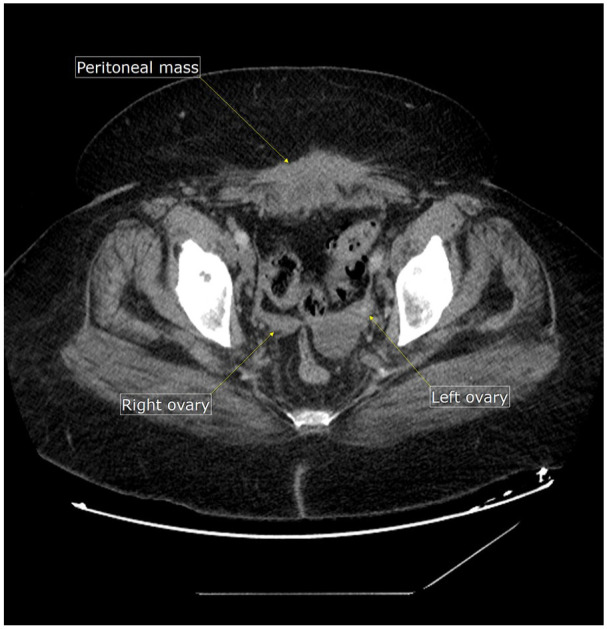

Ovarian cancer is the second most common gynecologic malignancy in the United States, with high mortality due to delayed diagnosis. Serum CA-125 is widely used for screening and monitoring but lacks sensitivity and specificity in some cases. We present a 67-year-old female diagnosed with advanced-stage ovarian cancer despite normal CA-125 levels, with elevated HE4 (human epididymis protein 4), underscoring its diagnostic value. This case highlights the importance of integrating HE4 with CA-125 in ovarian cancer evaluation and emphasizes a multimodal approach to enhance early detection and outcomes.